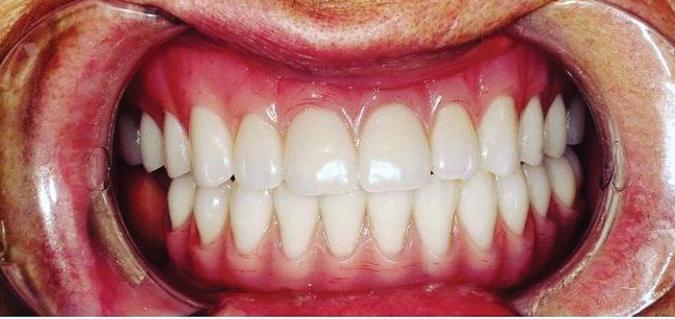

39 | Non-Extraction Orthodontic Treatment | Submitted By Let’s Smile Dental

Can just four implants replace all of the teeth on the top or the bottom of your mouth? Thanks to advances in dental implant technology, that answer is a resounding yes.

Believe it or not, tooth loss is extremely common among adults, especially as we age. In fact, more than 35 million people in America are missing all of their upper and/or lower teeth. Rather than living with the discomfort and hassles of dentures, many people are opting for what is called “all-onfour” dental implant restoration.

Here’s where it gets really interesting: You do not need a dental implant for each and every one of your missing teeth. All you need is four precisely placed implants on the top of your mouth, and four on the bottom, to restore your full smile. That’s the beauty of the all-on-four. And because the implant is made of titanium, it has the unique ability to fuse to living bone and function as part of it. So eventually, the dental implant becomes part of the jawbone and serves as a strong, long-lasting foundation for your new teeth.

Thanks to advances in dental implant technology, just four implants can replace all of the teeth on the top or the bottom of your mouth.

this bone fusion has another important benefit: it prevents future bone loss in the jaw. This helps to maintain a more youthful facial structure – and better oral health. But perhaps the biggest surprise about the all-on-four is how quickly it can transform your life.